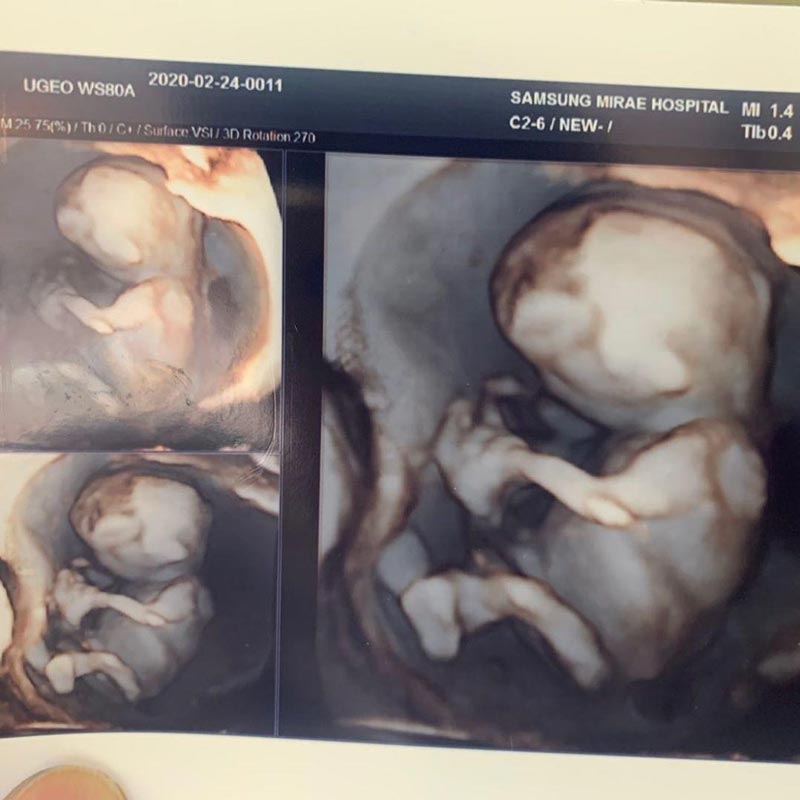

ภาพจาก Instagram auan_rangsit

เรียกว่าแฟน ๆ และเพื่อนในวงการบันเทิงต่างรอลุ้น และส่งกำลังใจให้อย่างเนืองแน่น หลังจากที่ อ้วน รังสิต ได้เปิดเผยข่าวดีว่าในวันนี้ (17 สิงหาคม 2563) ภรรยาสาวชาวเกาหลีใต้ มะม่วง หรือ ปาร์คฮยอนซอน ได้เข้าห้องผ่าตัดเตรียมคลอดลูกคนแรกแล้ว

ล่าสุด อ้วน รังสิต เผยคลิปวิดีโอของภรรยา ที่มาเล่าความรู้สึกหลังจากผ่าคลอด ระบุว่า ตอนผ่าตัดไม่รู้สึกอะไร เพราะว่าฉีดยาชา ซึ่งคุณหมอก็พูดคุยดี รู้สึกอบอุ่น ทำให้อยู่ดี ๆ ก็ร้องไห้ออกมา ยิ่งตอนที่หมอเอาลูกออกมาก็ยิ่งรู้สึกประหลาดใจว่าในท้องมีอีกหนึ่งชีวิตอยู่จริง ๆ

พอลูกออกมา คุณหมอก็อุ้มมาให้ดู ยิ่งทำให้มะม่วงร้องไห้หนักขึ้นไปอีก เพราะลูกน่ารักมาก บวกกับหลากหลายความรู้สึกที่ประดังประเดเข้ามา ทั้งดีใจ ตกใจ ประหลาดใจ ที่ตัวเองกำลังจะกลายเป็นแม่คนแล้ว